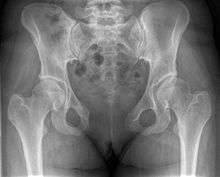

Diastasis symphysis pubis is the separation of normally joined pubic bones, as in the dislocation of the bones, without a fracture.

This abnormally wide gap can be diagnosed by radiologic studies such as x-ray, MRI, CT scan or bone scan. Manual testing by a healthcare professional can also be used. The patient is placed in various positions and pressure is applied in such a way that it provokes pain and maybe movement in the pubis.

X-ray

An X-ray film will show a marked gap between the pubic bones, normally there is a 4–5 mm gap but in pregnancy, hormonal influences cause relaxation of the connecting ligaments and the bones separate up to 9 mm. To demonstrate instability of the joint the patient is required to stand in the "flamingo" position, (standing with weight on one leg and the other bent).[1] A vertical displacement of more than 1 cm is an indicator of symphysis pubis instability.[2] A displacement of more than 2 cm usually indicates involvement of the sacroiliac joints.